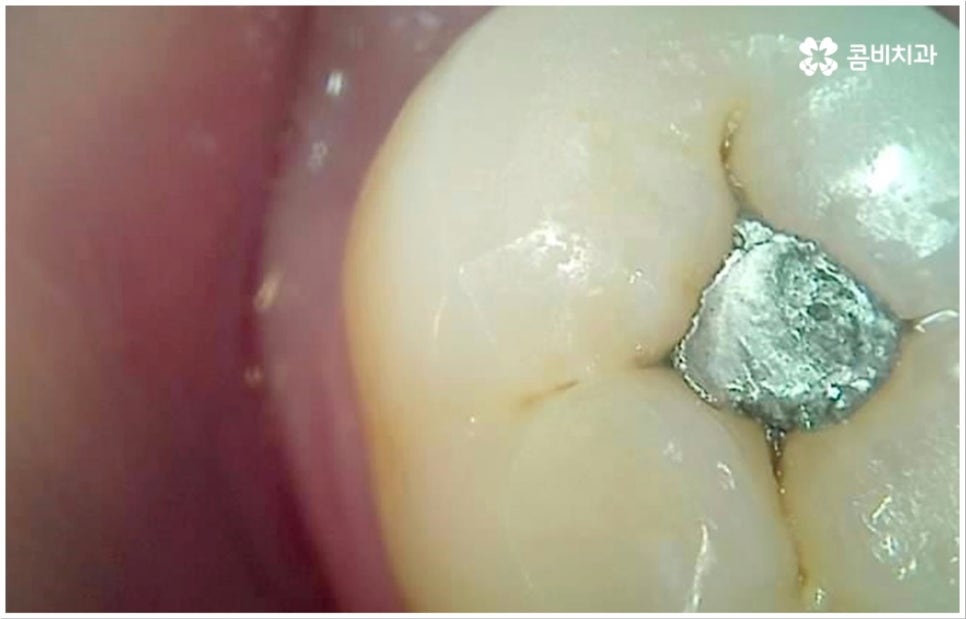

흔히 치과를 찾게 되는 원인 중 하나인 충치는 보통 위아래 치아가 맞닿는 교합면, 즉 우리가 식사를 할 때 음식물을 잘게 자르고 갈아주는 역할을 하는 씹는면에 발생할 가능성이 가장 크다고 할 수 있습니다. 그 이유는 교합면의 모양을 생각해 보면 잘 알 수 있는데요. 한 예로 우리가 거울 앞에서 입을 크게 벌렸을 때 쉽게 살펴볼 수 있는 아래 어금니의 교합면을 생각해 보면 윗면이 평평한 게 아니라 볼록하게 올라온 부위(교두)와 그 사이의 깊은 홈(구)으로 이루어져 있기 때문에 식사 후 치아 사이나 이 홈 부분에 음식물 찌꺼기나 침 등이 잔존할 가능성이 많은데, 이를 깨끗하게 제거해 주지 않으면 여기서 세균이 급증하여 충치 등 구강 질환이 발생할 빈도수도 높아지게 되는 거예요.

이러한 교합면 충치는 비교적 관찰이 쉽고 접근 역시 용이하기 때문에 조금만 주의를 기울이면 충분히 예방 또는 초기 치료를 할 수 있습니다. 물론 완전 초기 단계에서는 신경이 없는 치아 겉면인 법랑질부터 우식이 일어나기 때문에 충치 통증 도 거의 없고 육안으로 구별해 낼 수 있는 특징 (색깔 변화 등) 도 미미하므로 환자분들의 입장에서 충치가 발생했다는 것을 인지하기 어려울 수 있어요. 이와 같이 자기도 모르게 발생했을지 모를 충치에 대해 예방 및 조기 대처를 하기 위해서는 1년에 한 번 또는 두 번 정도 치과에 정기적으로 내원하셔서 꼼꼼하게 검진을 받으시는 것이 구강 건강을 지키기 위한 보다 바람직한 방법이 될 거예요.

여기서 우리가 더욱 주의를 기울여야 할 점은 병증이 조금 더 진행되어 자각 증상이 막 생겼을 때 시기를 놓치지 않고 바로 치료를 받아야 한다는 데 있어요. 이 때도 비교적 초기에 속하기 때문에 손상이 일어난 부위만 깨끗하게 삭제하고 레진으로 직접 때워주는 방식으로 치료할 수 있는 케이스가 대부분일 거예요. 물론 치료 내용은 자세한 상황에 따라 달라지겠지만 보통 약간 시리거나 찌릿하는 충치 통증 을 처음 느끼는 것은 법랑질 안 쪽의 상아질에 손상이 막 일어나기 시작하는 무렵이므로 이 시기에는 좀 더 빠르고 (보통 하루 만에 치료가 끝남) 간편한 직접 수복이 가능하기 때문에 환자분들의 입장에서도 의료진의 입장에서도 치료가 수월하며, 자연 치아의 삭제량이 적은 만큼 앞으로 관리를 잘 해 주면 해당 치아의 수명이 보다 길어질 수 있다는 점에서 구강 건강에 훨씬 유리하니 이 점을 유념하시고 치과 내원을 미루지 않으시길 권유드리고 있습니다.

치아 가장 안 쪽의 신경관까지 세균으로 오염되었다면 신경 치료를 통해 변성된 신경을 제거하고 신경관(근관)을 소독 밀봉한 후 남아 있는 자연 치아를 보호하기 위해 크라운을 씌우게 되는데, 환자분들 중에 이러한 보철치료 후 더이상 시리거나 쑤시는 등의 충치 통증 이 느껴지지 않아 해당 치아에 앞으로 남은 평생 아무런 문제가 생기지 않을 거라 오해하시는 분들이 더러 있어요. 하지만 보철물에도 수명이 있기 때문에 주기적으로 마모 정도 및 미세 파절 여부를 검진한 후 필요시 교체해야 하며 시간이 지나면서 보철물과 치아 사이 미세한 틈이 발생할 수 있어 그 사이로 세균이 침입한다면 2차 충치가 유발될 가능성도 있으니 주의하실 필요가 있습니다.

통상적으로 보철물의 주기는 10년이라고 알려져 있으나 환자분들의 평상시 식습관이나 구강위생 관리 여부 등에 따라 자세한 상황은 달라질 수 있기 때문에 지속적인 관찰을 통해 파절, 탈락, 2차 충치 등의 문제가 생기지 않도록 관리하는 것이 중요하다고 할 수 있어요. 특히 신경이 제거된 상태라면 충치 통증 을 느끼지 못할 것이므로 혹여 치아를 살리기 어려울 정도로 2차 충치가 심각해 질 때까지 발견하지 못하는 상황이 생기지 않도록 정기 검진을 철저하게 하고 스케일링 치료를 통해 구강 내부를 청결하게 유지해 주는 것이 필요할 거예요.